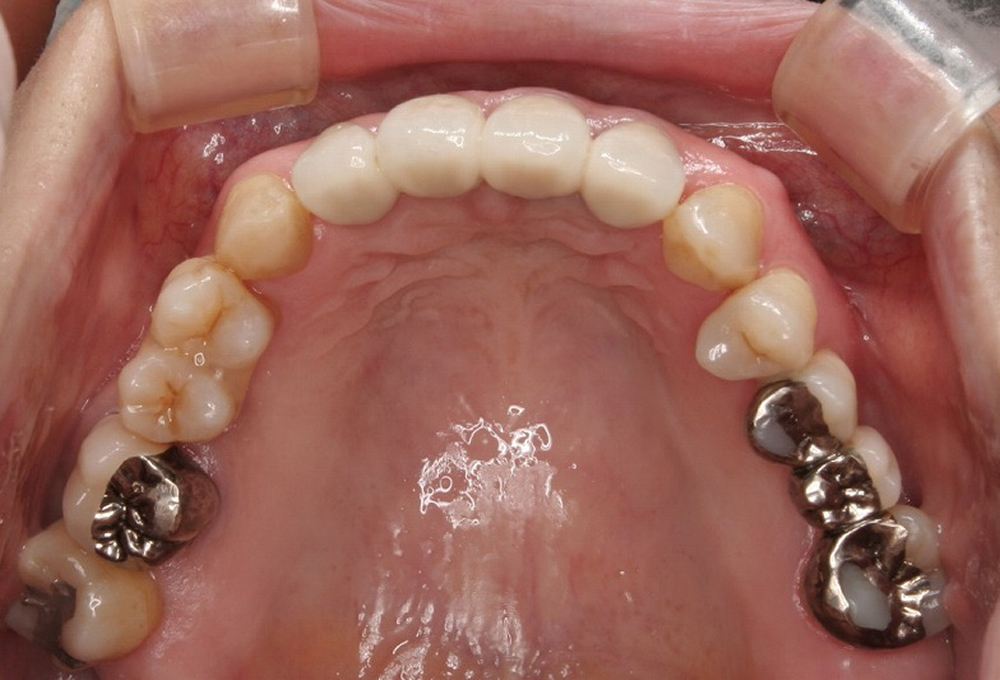

⑩術後 上顎